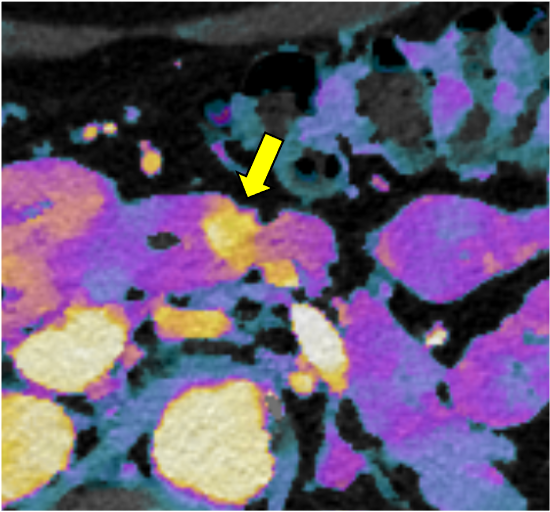

膵ダイナミックCTの膵実質相120kVp画像(図1)で膵体部に限局性萎縮(赤矢印)を認めるが、膵癌を疑わせるような低吸収域は同定できない。遅延相120kVp画像(図2)では萎縮部近傍にごく淡い高吸収域(黄矢印)を認め、線維性間質に富む膵癌の可能性が示唆される。Dual-energy CTの仮想単色低エネルギー画像(図3)およびヨード密度画像(図4)では遅延濃染域が明瞭化しており、膵癌の診断確信度が向上する。膵体尾部切除術が施行され、高分化型浸潤性膵管癌(腫瘍径6mm、pT1a)と最終診断された。術後、補助化学療法が行われ、現在まで無再発で経過している。

CT技術や撮像プロトコル設定について